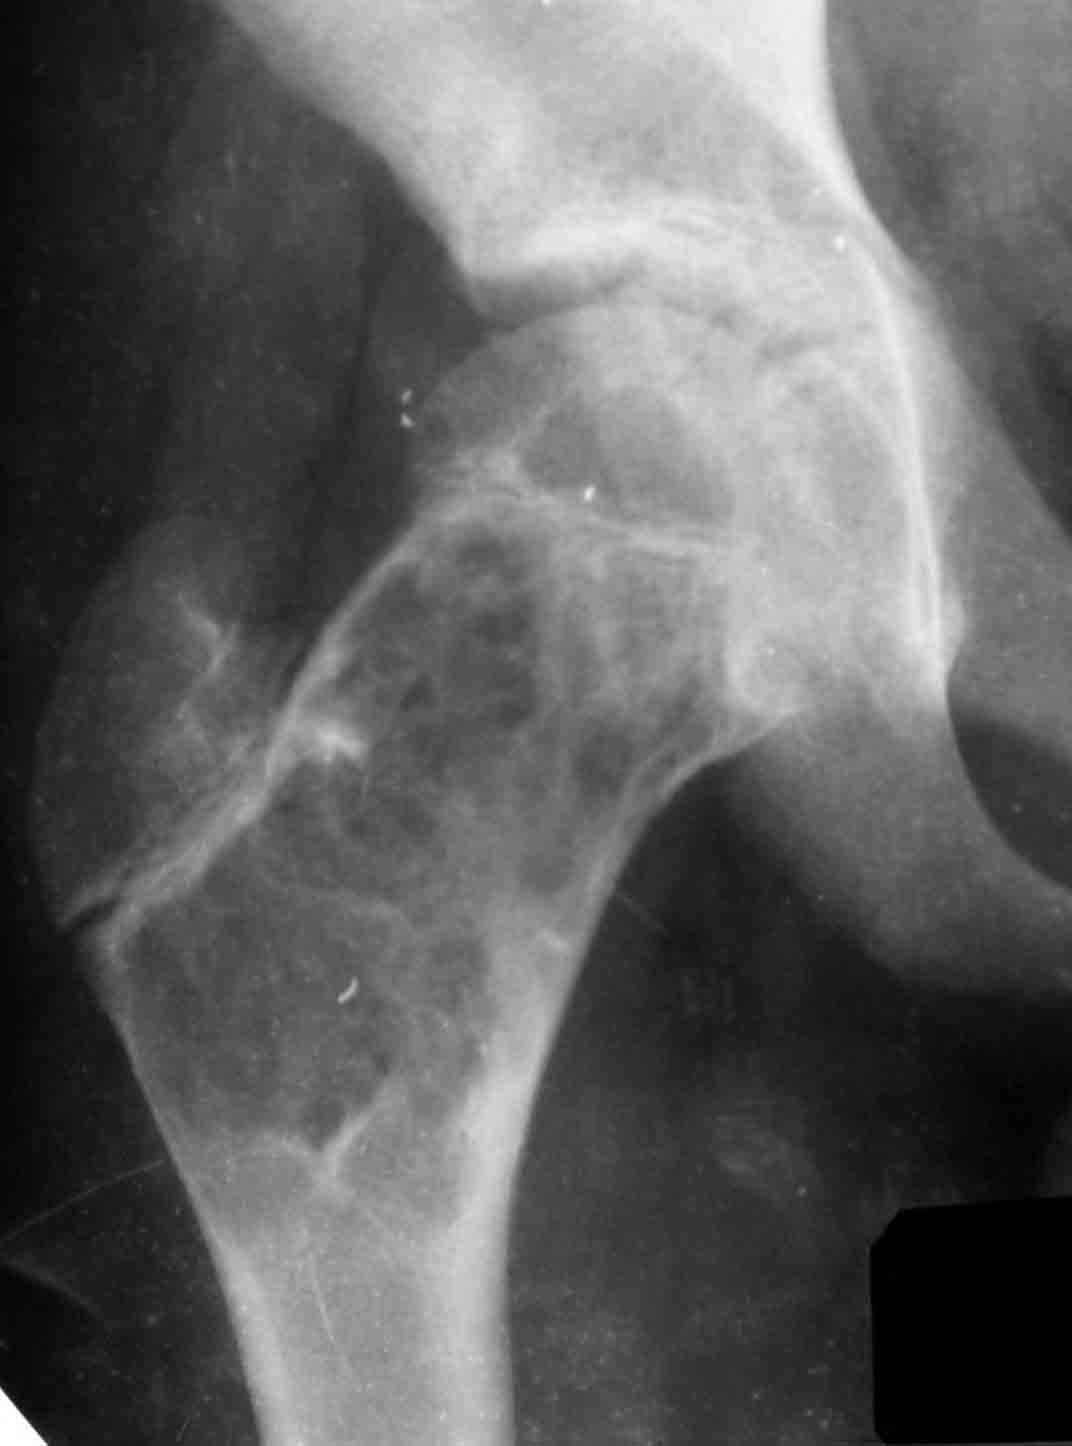

Дабы не уводить в офтопик вопрос о несросшемся переломе бедра, хочу добрым словом упомянутьколлапан - доступный и эффективный российский продукт, который судя по публикациям на форуме не нашел еще должного распространения в повседневной практике. Чтобы не быть обвиненным в рекламе или личной заинтересованности скажу, что работаю я в Казахстане, где большинство последних российских разработок не прошло регистрацию( отдельный вопрос почему?) и коллапан завозят родственники пациентов из соседних сибирских городов. За тридцать лет практики многократно возникали ситуации в которых остро чувствовалась проблема материала для заполнения костных дефектов- от открытых переломов до дефектов при секвестрэктомиии и удаления кистозных опухолей. Риск аутопластики в инфицированную среду или дефицит донорской кости у детей, повсеместное закрытие лабораторий консервации тканей, высокая стоимость зарубежных остеоиндуктивных материалов делают коллапан одним самых доступных материалов в exUSSR \простите за пафос\. В нашем отделении мы применяем коллапан в гранулах с антибиотиком для пристеночной пластики при удалении секвестров при послеоперационных и посттравматических остеитах, при остеосинтезе ложных суставов и заполнении костных дефектов. Коллапан не может применяться в ситуациях где имплантату необходима опорная функция, но это уже другая песня. Привожу пример 15 летнего пациента с обширной фиброзной дисплазией проксимального бедра, которого я оперирован в ноябре 2005, контрольный снимок от 3-2006.

Произведена подвертельная трепанация, кюретаж и рыхлое заполнение гранулами коллапанаГ полости, ушло до 100 куб см гранул. Иммобилизация не проводилась, нагрузка на ногу разрешения через 5 мес, сейчас подросток активно отдыхает на каникулах. Аваскулярный некроз головки вроде не предвидится, думается, что в процессе роста кисты коллатеральное кровообращение сформироваласьдостаточно, о судьбе ростковой зоны можно будет говорить через год. Кстати в одном НИИ ему былапредложена операция эндопротезирования. Первые 2 мес